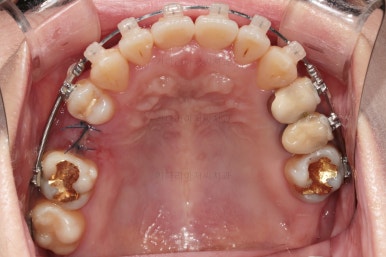

임플란트 할 공간도 여유롭게 마련이 되었네요.

임플란트는 뿌리 부분 식립 -> 3~6개월 기다림(뼈와 임플란트가 단단히 붙을 시간이 필요) -> 머리 부분을 완성하고 마무리

따라서 교정치료가 100% 끝나기 전에, 임플란트 공간만 마련되면 바로 식립을 하게 됩니다.

임플란트 뿌리 부분이 먼저 식립되었고요.

뼈와 잘 붙으라고 잇몸을 잘 꼬메어 줍니다.

최종 보철이 올라갈 3~6개월 기간동안 디테일한 조절을 더 해주고 교정과 임플란트를 동시에 마무리 합니다.

임플란트 보철이 깔끔하게 들어갔고, 교정치료도 마무리가 되었습니다.

화살표 부분은 임플란트가 안들어갔는데요.

약간의 우여곡절이 있긴했었지만 엄밀히 따지면 위아래가 지그재그로 껴들어가는 교합의 특성상 윗니는 1개 모자라도 교합에는 크게 문제가 없답니다.

해당 부분을 임플란트를 해주면 좋겠지만 환자분도 충분히 고민 후에 원하실 때 식립을 하기로 마무리르 하였습니다.